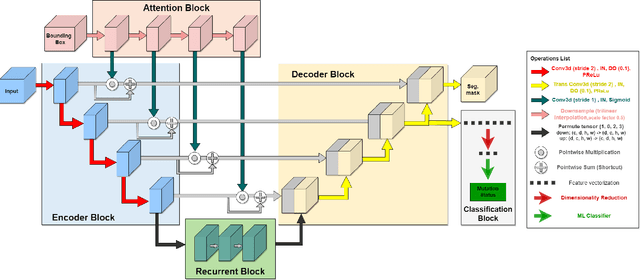

Lung cancer is a leading cause of death worldwide. Early-stage detection of lung cancer is essential for a more favorable prognosis. Radiogenomics is an emerging discipline that combines medical imaging and genomics features for modeling patient outcomes non-invasively. This study presents a radiogenomics pipeline that has: 1) a novel mixed architecture (RA-Seg) to segment lung cancer through attention and recurrent blocks; and 2) deep feature classifiers to distinguish Epidermal Growth Factor Receptor (EGFR) mutation status. We evaluate the proposed algorithm on multiple public datasets to assess its generalizability and robustness. We demonstrate how the proposed segmentation and classification methods outperform existing baseline and SOTA approaches (73.54 Dice and 93 F1 scores).